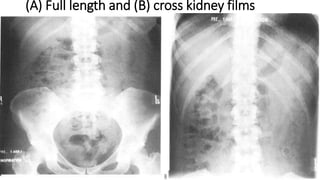

(A) Full length and (B) cross kidney films

The outline of several anatomical structures can be seen